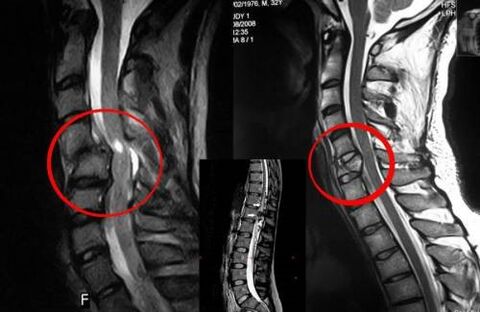

Skriemeļu osteohondrozei nepieciešama savlaicīga ārsta konsultācija, kas palīdzēs atjaunot bojāto muguru. Mūsdienu aprīkojums ļauj veikt diagnozi agrīnā attīstības stadijā. Patoloģijas gadījumā sazinieties ar neirologu vai ortopēdu. Vispirms tiek veikta ievainotā mugurkaula izmeklēšana un anamnēzes apkopošana, pēc tam tiek noteiktas laboratoriskās un instrumentālās diagnostikas metodes, kas identificē osteohondrozi:

- rentgena starojums;

- mielogrāfija;

- neiroloģiskā izmeklēšana;

- CT un MRI;

- kodolmagnētiskā rezonanse.